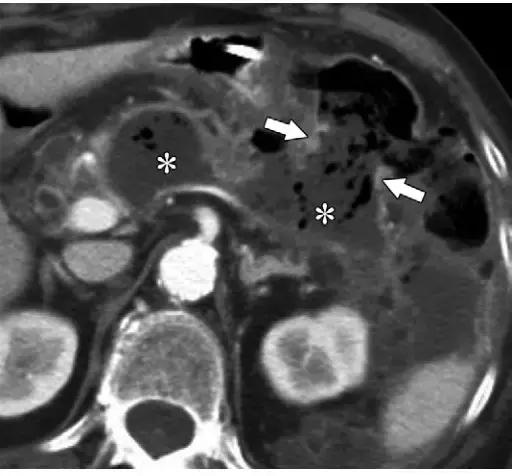

ANCs 发生于发病 4 周内的坏死性胰腺炎,其内含有坏死物,多见于小网膜囊和肾周,也可发生于胰腺实质内。他们可为多灶性,有分隔,可延伸至盆腔。

ANCs 也含有大量液体,和 APFCs 的鉴别是 ANCs 含有非液性成分,比如实性成分或脂滴。如果有碘对比剂禁忌证,平扫 CT 如果能发现脂性密度对确定坏死及诊断 ANCs 具有重要帮助(图 9)。

在胰腺炎早期,APFC 和 ANC 的鉴别比较困难。发病后 2 周的影像学检查对鉴别两者具有重要意义。所有与坏死胰腺实质相通的胰周异常病灶即使看不到非液性碎片也应诊断为 ANC。

图 8 一名 25 岁男性自发性胰腺炎患者增强冠状位图像示感染性 WON。a 发病 7 天,双侧肾周间隙可见明显 ANCs。ANCs 扩散至盆腔(*),为不均质液性密度,含有实性坏死成分,其中包括脂滴(箭头)。b 发病 15 天,坏死物(*)更容易辨认,坏死脂肪也更易辨认(箭头)。 c 发病 43 天患者因败血症再次入院,肾周可见不均质含气密度,周围可见增强的厚壁(箭头),符合感染性 WON 的诊断